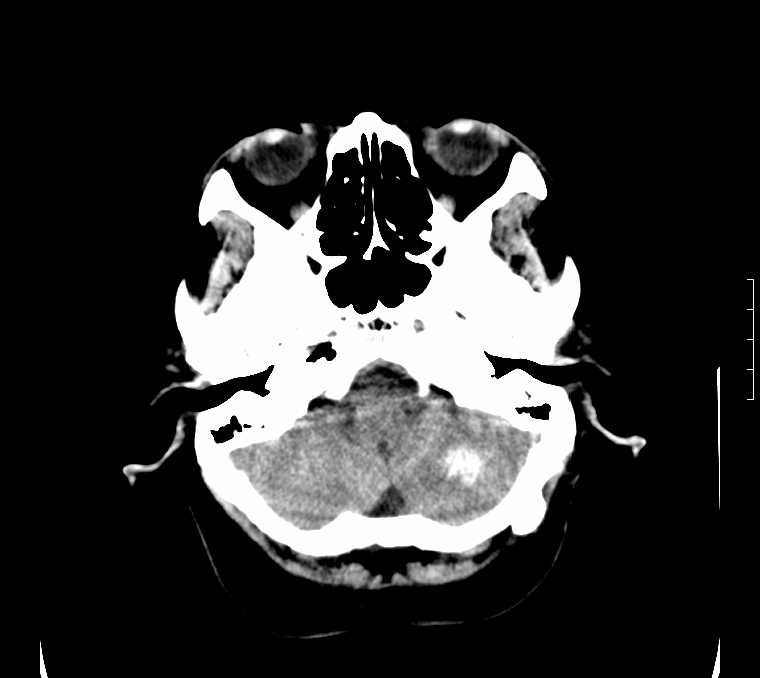

标题: CT24387:看看这例脑部改变!!

老年女性。头晕。

考虑:甲旁减。

fahr病

鉴别于特发性家族性脑血管亚铁钙沉着症(fahr`s病)与甲状旁腺机能低下之间,请结合临床及相关实验室检查。